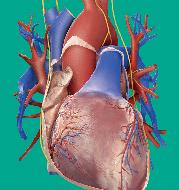

Lidé kdysi věřili, že srdce je sídlem myšlení a citu, dnes však víme, že je to svalová pumpa, která neúnavně pracuje, aby udržela krev v pohybu.

Na rozdíl od jiných svalů v těle, které si po námaze potřebují odpočinout a na chvíli se zastavit, je srdce předurčeno pracovat nonstop. Bije 70krát za minutu, 100 000krát za den, 40milionkrát za rok a za průměrný život napumpuje tolik krve, že by naplnila tři obří tankery. S každým úderem vytlačí okolo jednoho plného šálku krve a vyvíjí dostatečnou sílu, aby udrželo proudění krve ve 100 000 km cév v těle. Nepřetržitá dodávka čerstvé krve je pro tělní buňky životně důležitá, protože bez ní by během pár minut zahynuly na nedostatek kyslíku.

Plicní tepna

Tato céva přivádí odkysličenou krev do plic, aby tam nabrala čerstvý kyslík.

Bijící srdce

Srdce je uvnitř duté, má silné stěny z výkonných svalů a je asi tak velké jako zaťatá pěst – a stejně tak silné. Horní část srdce je připojena ke spleti vysoce odolných cév. Krev proudí dovnitř cévami zvanými žíly a naplňuje vnitřní prostory srdce. Když srdce bije, svalové stěny se stahují a vytlačují krev ven cévami zvanými tepny.

Aorta Tato velká céva vede okysličenou krev ze srdce.

Svalová stěna Srdce je poháněno silnou svalovou stěnou, která se při každém úderu stahuje.

Osrdečník

Srdeční sval je obklopen pevným pláštěm zvaným osrdečník, který ho chrání před nárazy.

Uvnitř srdce

Srdce je rozděleno na dvě poloviny, takže pracuje jako dvě pumpy v jedné. Pravá polovina pumpuje odkysličenou krev do plic, aby zde nabrala vzdušný kyslík. Levá polovina pumpuje okysličenou krev do těla.